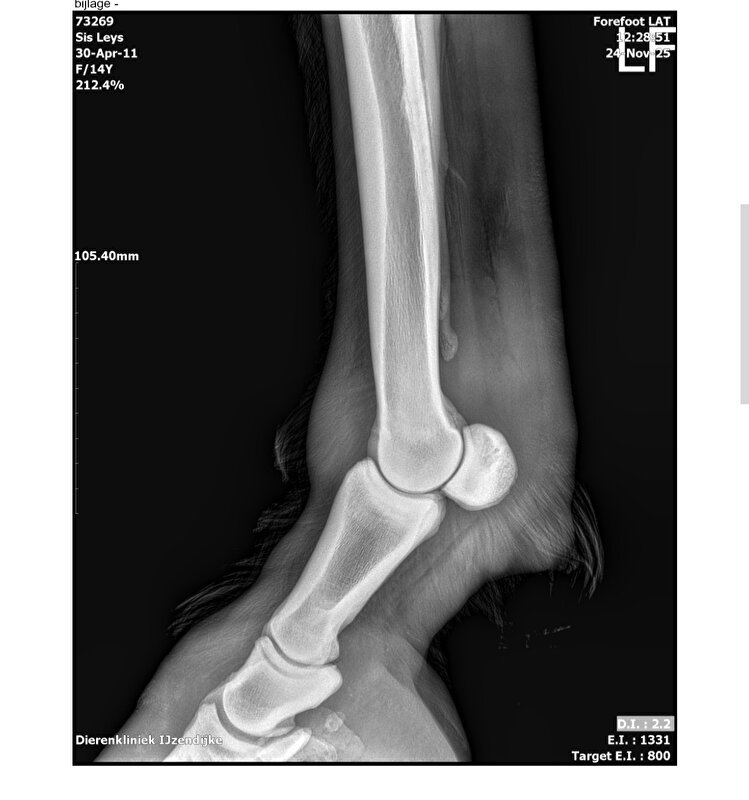

In oktober 25 was mijn pony licht kreupel aan het kogelgewricht links voor. Dit was vooral in draf te zien. Week metacam en het was beter. Half november was het echter slecht. Er is een echo en röntgenfoto genomen. De echo heb ik niet maar de röntgenfoto's wel. Doc zei ontsteking kogelgewricht. Dus wederom op metacam. Het mank lopen was vooral te zien op de volte als het slechte been aan de buitenkant zat. December en januari blijvend metacam gegeven en in februari afgebouwd naar nul omdat het zogezegd over was. Ik stuurde wekelijks een filmpje naar de doc. Je kan al raden... Het is terug. Zelfde symptomen. Ook de buigproef was negatief.

Van de röntgenfoto's kan ik persoonlijk niets maken. Is er iemand die hier advies in heeft? Doc zegt wrs mistrapt maar ik vind dit raar dat ze dit nu wéér heeft... In 14jaar heeft ze dit nog niet gehad...

Die fotos zien er heel goed uit. Ik zou inderdaad ook even een second opinion vragen. En ik vind zomaar pijnstillers voorschrijven ook wel wat apart bij een gewrichtsontsteking (volgens mij is dit vaak gewoon beginnende artrose? Correct me if I'm wrong). Ik had dan liever voor het inspuiten van het gewricht gekozen om direct bij probleem plek te kunnen behandelen.

Het gewricht ziet er mooi uit op de foto. Als het ontstoken zou zijn dan zou er waterdunne gewrichts vloeistof uit komen als men er een naald in steekt om te infiltreren met hyarulon en een steroide om de ontsteking te genezen.

Dit gewrichtsvocht moet stroperig zijn om het te smeren namelijk.

Als dit waterdun blijft dan raakt het gewricht beschadigd en dat is dan artrose

Ja ik ga een second opinion vragen. Foto's zijn er eind november gemaakt toen het slechter was dan nu. Mijn huidige doc spreekt niet over inspuitingen met wat dan ook. Ik vind dit ook raar. Op de foto's en echo was blijkbaar geen arthrose te zien.